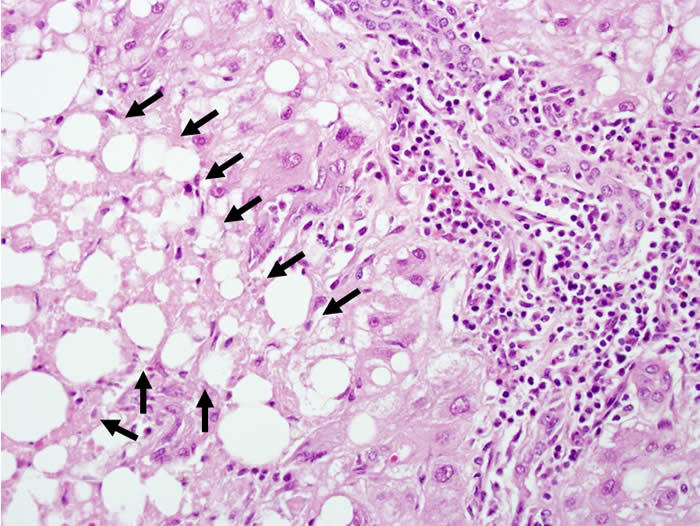

病理解读:肝细胞肝板结构基本正常,有点状坏死及炎症侵犯,病变汇管区为主,有嗜酸小体及肝细胞肿胀,肝细胞淤胆,炎症细胞以淋巴细胞多见,少量嗜酸粒,胆管增生明显,胆管破坏不明显,未见纤维化。总体印象,急性肝炎样变化。

与其他类型的病毒性肝炎相比,人类HEV感染的组织病理学的信息较少。急性戊型肝炎肝损伤的典型模式类似于其他形式的急性肝炎中发现的典型病变。包括肝细胞膨胀、凋亡(嗜酸)体散落以及汇管区淋巴细胞浸润。中性粒细胞在实质和汇管区中相对常见,这在其他类型的病毒性肝炎中少见,淋巴细胞是主要的浸润细胞类型。对HEV感染常有胆汁淤积。可以是轻度或中度的可有胆小管堵塞,并导致肝细胞肿大并呈菊团样排列,特别是在汇管区周围区域。一些临床非常明显的胆汁淤积型案例在病理学可能较少的肝细胞损伤,戊型肝炎的胆汁淤积形式可能类似于甲型肝炎病毒(HAV)感染。胆汁淤积也可见破坏性胆管炎。严重的情况下,可能存在广泛的肝细胞坏死和实质塌陷,伴有明显的导管反应。

戊型肝炎。(A)H&E染色。汇管区周围实质包含明显的导管反应,其特征在于小胆管增殖,邻近肝细胞紊乱,扩张的胆小管和导管中可见明显的胆汁栓。轻度淋巴细胞浸润和邻近的实质分散。(B)H&E染色。来自同一患者的高放大倍率图像。在扩张的小管中明显的胆汁淤积,在右侧明显导管反应的界面处形成小胆汁湖,并且肝细胞(a)轻度空泡,缺乏正常的肝窦排列。比例尺,100 μm。